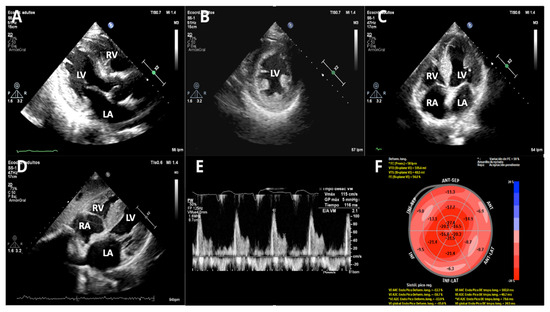

| Echocardiography | Widely available; detects LVH, diastolic dysfunction; apical-sparing GLS suggests amyloidosis; RV/atrial involvement visible | Limited specificity; wall thickening non-specific; cannot type amyloid | Suggests amyloidosis but cannot distinguish ATTR from AL |